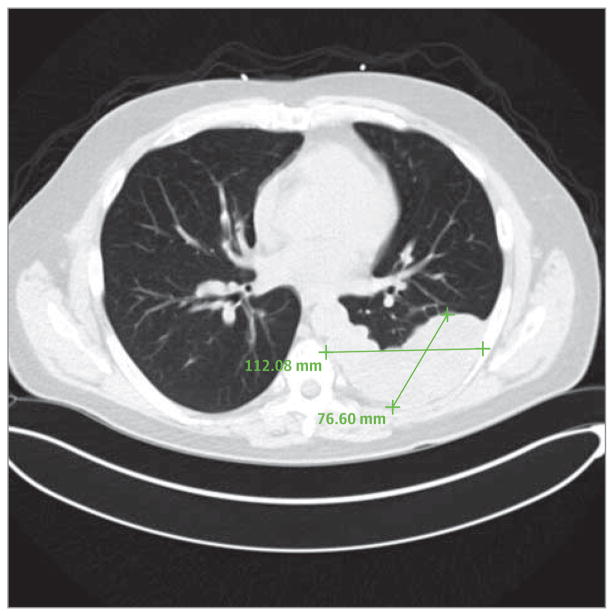

He presented to the emergency department at our institution for palpitations and chest pain. His initial workup was notable for sinus tachycardia with a heart rate of approximately 180 beats per minute with negative troponin levels but markedly elevated creatinine kinase and creatinine kinase–MB fraction levels. He was given aspirin, clopidogrel bi-sulfate, and intravenous heparin sodium and admitted to the cardiology service. The results of serial testing for troponins were negative, and his abnormal test results were attributed to tachycardia-induced demand ischemia. The results of an exercise stress test and an echocardiogram were unrevealing. Computed tomography of his chest revealed a large, pleural-based mass of soft tissue (Figure). The cardiology team noted diffuse muscle twitching in the patient’s limbs and consulted neurology.

Figure. Computed Tomographic Scan of the Chest Revealing Recurrent Thymoma.

A 12 × 4.5 × 17-cm lobulated mass of soft tissue is revealed in the dependent aspect of the left hemithorax, abutting the pleura. A biopsy confirmed the mass to be recurrent thymoma.